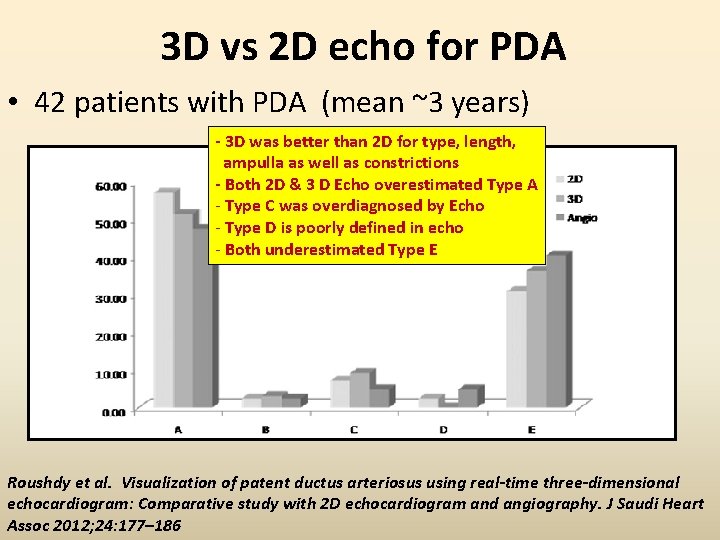

3 D vs 2 D echo for PDA • 42 patients with PDA (mean ~3 years) - 3 D was better than 2 D for type, length, ampulla as well as constrictions - Both 2 D & 3 D Echo overestimated Type A - Type C was overdiagnosed by Echo - Type D is poorly defined in echo - Both underestimated Type E Roushdy et al. Visualization of patent ductus arteriosus using real-time three-dimensional echocardiogram: Comparative study with 2 D echocardiogram and angiography. J Saudi Heart Assoc 2012; 24: 177– 186